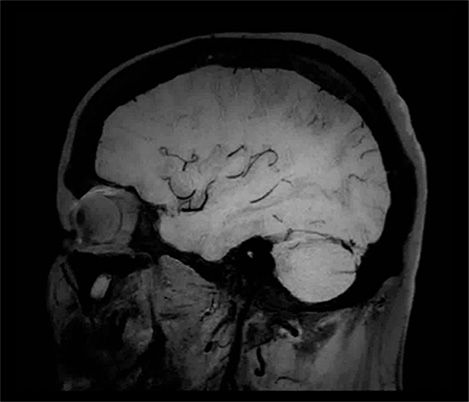

At the Rothschild Foundation Hospital in Paris we run most of our post contrast T1 TSE sequences with MSDE black blood suppression because it is easier to interpret the data with the high signal from small vessels removed to optimize conspicuity of contrast enhancing lesions.

Dr. Savatovsky, Fondation Rothschild, Paris, France